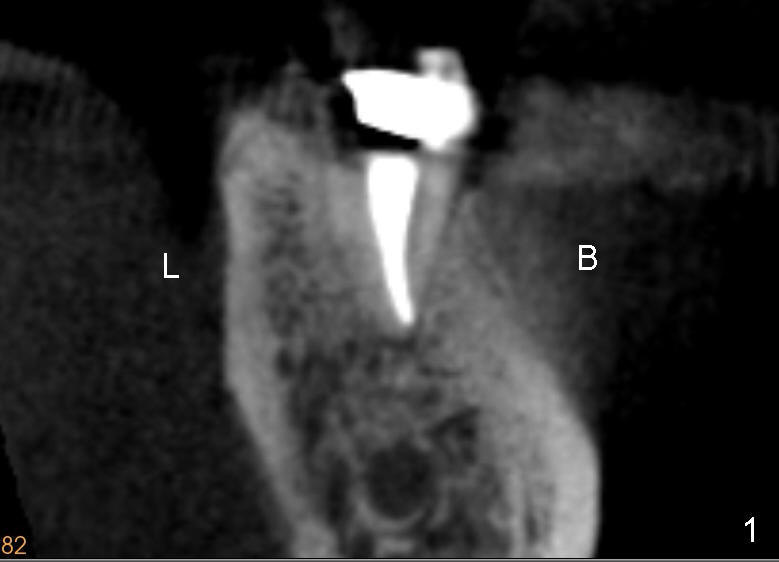

The root of the lower molar is more or less situated buccally, as shown in Fig.1 (coronal section of the distal root of a 2nd molar). If osteotomy follows the path of the original socket (black shadow in Fig.2 (Fig.1 after extraction)), the buccal plate (<) would be thin and low when an implant is placed.

To overcome this problem, a pilot drill penetrates the buccal slope of the lingual wall (Fig.3 red line). Once the pilot drill gets "bite", change its direction to finish osteotomy (Fig.4). When subsequent drills are being used, lean each drill lingually, against "natural" tendency of the drill sliding buccally.